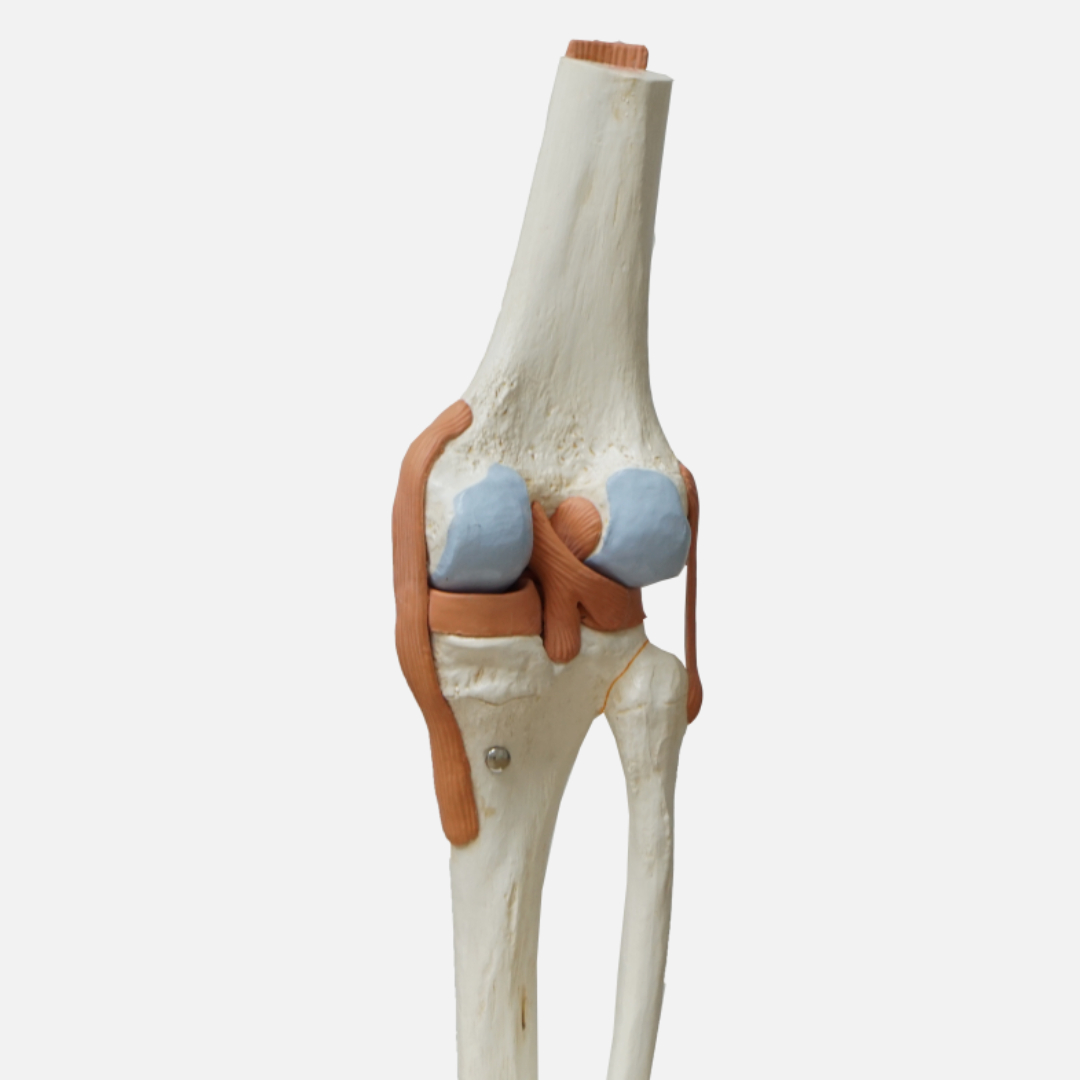

우리 몸의 뼈와 뼈 사이에는 '연골'이라는 조직이 있어요. 마치 뼈 사이의 쿠션처럼, 움직임을 부드럽게 하고 충격을 흡수하는 역할을 하죠. 연골 덕분에 우리는 아프지 않고 자유롭게 움직일 수 있는 거예요.

하지만 연골은 한 번 손상되면 재생이 어렵다는 사실! 그래서 평소에 연골 건강을 잘 지켜주는 것이 매우 중요해요. 특히 나이가 들수록 연골은 점점 닳고 약해지기 때문에 더욱 신경 써야 한답니다.